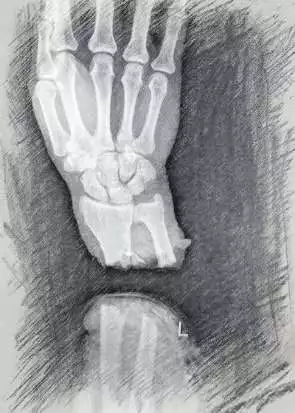

2018年12月29日,刘大叔锯木头时不慎被切割机锯到左前臂,导致左前臂完全离断成两截,手掌直接掉到地上,被家人紧急送往当地医院。当地医院见其伤势严重,简单包扎止血,断肢干燥冷藏处理后,建议其转入娄底市骨伤医院进行专业治疗。

刘大叔入院后,医院立即开通抢救绿色通道,经检查发现刘大叔左前臂近腕部约4厘米处横行离断,肌肉、肌腱撕断翻出伤口外,骨断端外露,伤口皮缘呈锯齿状,断端周围可见大量“锯木灰”样异物缠绕。在常温状态下,断肢(指)再植手术的有效时间在6小时左右,病人从新化送到骨伤医院已过去3个多小时,手术治疗迫在眉睫。为了赢得时间,肩肘手足科主任王胜冬和团队经过讨论,制定好手术方案,在保证患者生命安全的前提下积极抢救离断肢体,尽全力进行“左前臂离断肢体再植术”。

经过伤肢清创、骨折复位内固定、血管、神经、肌腱探查修复、血管吻合等等,手术用了整整7个小时,显微镜下可见断裂的血管、神经、肌腱被重新吻合,患肢色泽和温度逐渐恢复、毛细血管充盈,手术获得成功。术后经过抗炎、抗凝、抗痉挛等治疗,再植手臂完全成活。